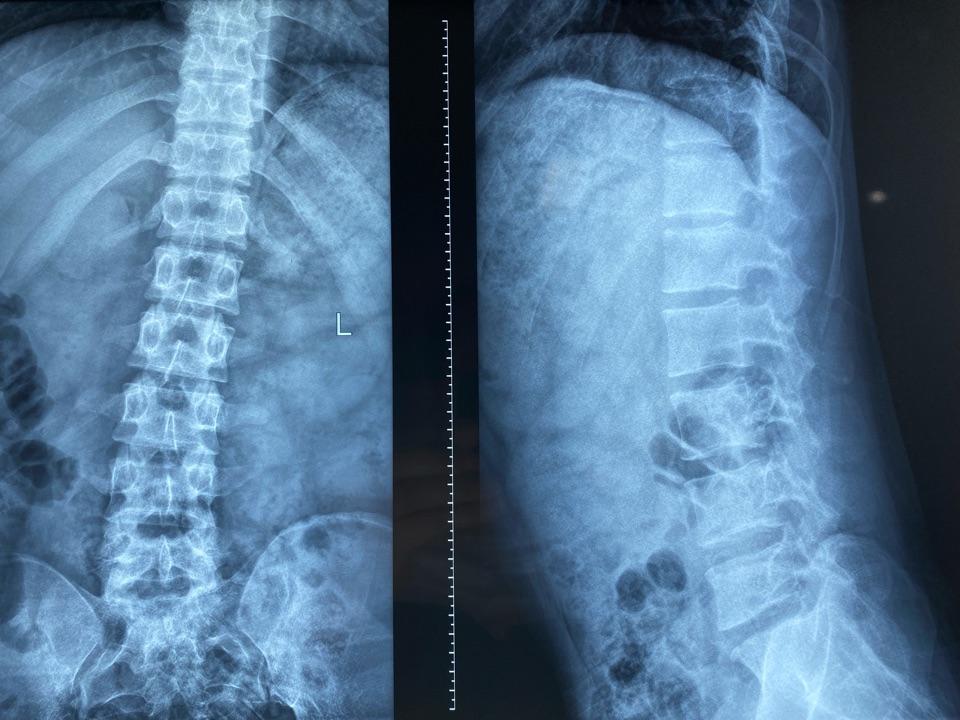

腰椎正侧位片:疼痛导致的脊柱侧弯